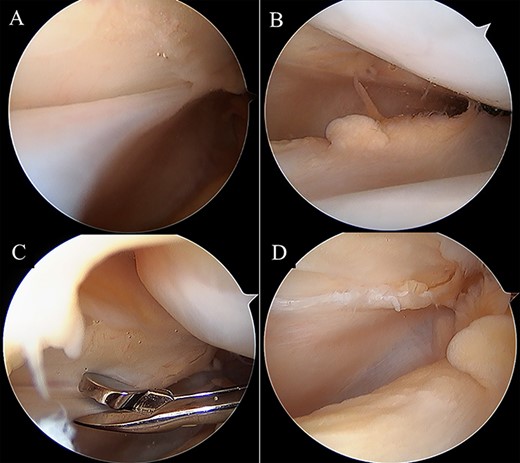

Two months postoperatively, the patient presented with the pain in the medial margin of the patella during walking and knee extension, and the pain continued when she was allowed to start rhythmic gymnastics at 6 months postoperatively. There was no evidence of swelling, crepitus and ROM restriction, and her apprehension sign was also negative. Pain was relieved by an intra-articular xylocaine injection. Postoperative MRI showed no clear injury to the cartilage of the medial PF joint, and the medial PF joint space and the size of the medial plica were almost the same as before surgery (Fig. 2). Based on these findings, left medial plica syndrome was suspected. Although the patient underwent conservative treatment consisting of analgesics and physiotherapy, there were no signs of improvement, and consent was obtained for undergoing arthroscopic surgery at 8 months after the initial surgery. Intraoperative arthroscopic findings with probing confirmed an unenlarged but hardened and thickened medial plica (Fig. 3). No injury to the patellar and femoral cartilage was observed. The synovial plica was considered the main cause of pain, and we performed a partial resection of the medial synovial plica. The pain and the tenderness at the medial margin of the patellar during walking and exercising had gradually improved after surgery. The Lysholm scale improved from 85 to 100 points. At 2 years postoperatively, the patient has currently no pain in the medial side of the patella, negative apprehension sign. She has returned to play in rhythmic gymnastics.

MRI. Axial proton density-weighted (TR = 3000, TE = 12) image before medial patellofemoral ligament (MPFL) reconstruction revealing medial synovial plica (white arrow). The medial patellofemoral joint space and the size of the medial plica after MPFL reconstruction are almost the same as before surgery. There are no clear signs of injury to the cartilage in the patellofemoral joint.